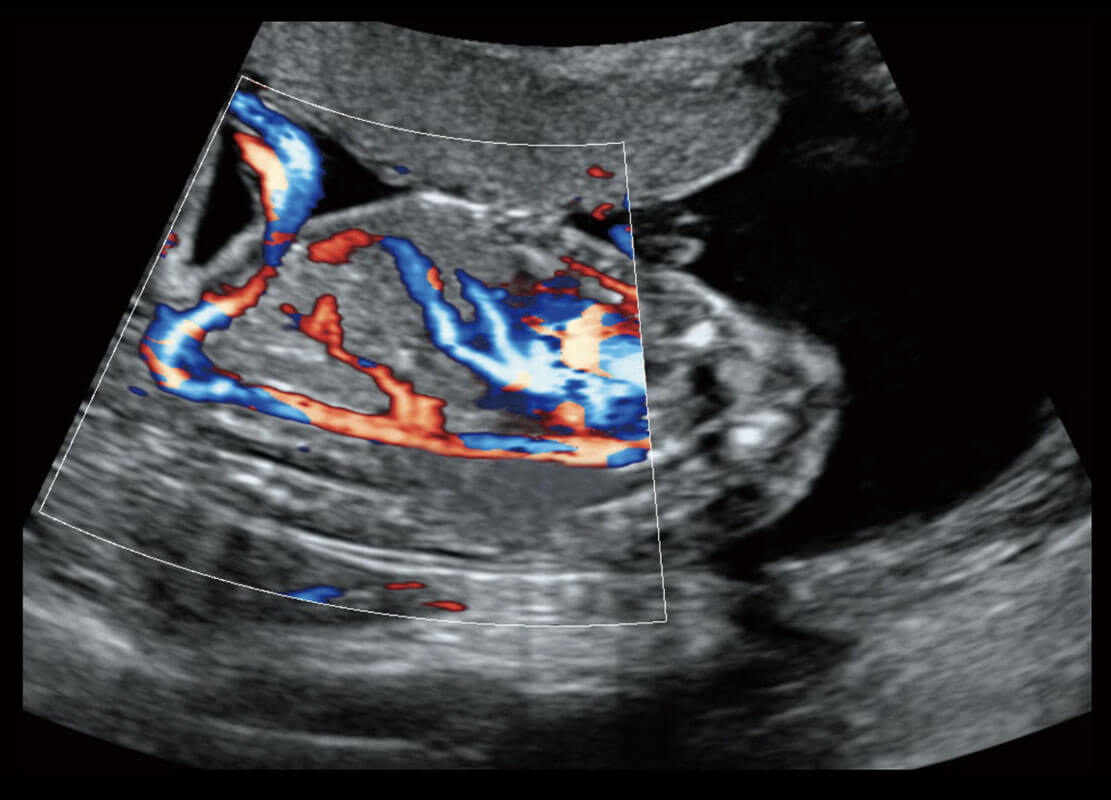

胎儿体循环

P60搭载一系列胎儿心脏成像技术,实现精细的胎儿心脏评估。